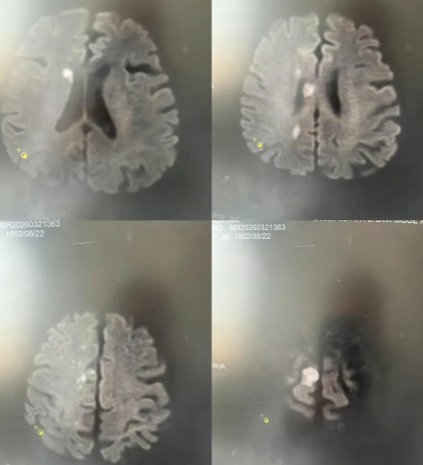

73岁的范大叔(化名)因“左侧肢体活动不利、言语不能1天”紧急入院。据悉,患者既往有9年脑梗死病史及50年吸烟史,入院时NIHSS评分9分,左侧肢体肌力3级、左下肢肌力0级,同时伴随心房率缓慢、胸闷气短等症状。头颅CT检查提示,患者双侧基底节、放射冠区多发腔隙性脑梗死,被明确诊断为急性脑分水岭梗死,病情危重,若不及时干预,可能导致神经功能永久性损伤,甚至危及生命。

时间就是大脑,我院卒中中心团队第一时间启动卒中救治流程,争分夺秒开展诊疗工作。团队快速完善头颅MRI、MRA及颈部血管超声等相关检查,精准明确脑血管病变具体情况,同时全面排查心源性因素,为制定诊疗方案提供坚实依据。结合患者病史、症状及检查结果,团队为其量身定制了集药物治疗与病情监测为一体的个体化方案,规范应用改善循环、建立侧支循环、抗血小板聚集及调脂稳定斑块等药物,同步开展心电监护、戒烟宣教及血栓风险评估,密切监测患者脑水肿变化与神经功能恢复情况,全程精准把控治疗细节。